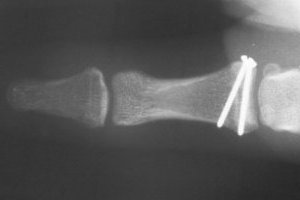

The completed repair:

and a film showing the bone anchor and a temporary transarticular pin.